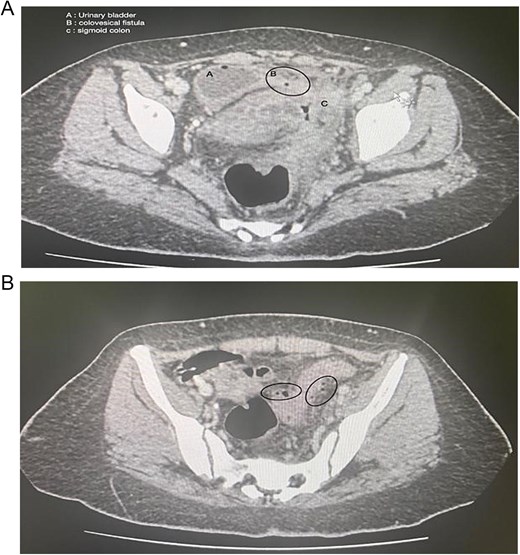

Colonoscopy showed severe luminal narrowing between the junction of the sigmoid and descending colon. Diagnostic cystoscopy confirmed the presence of a fistula opening and demonstrated a villous-like reaction in the urinary bladder mucosa, consistent with a fistulous connection. The fistula opening was located low, raising the possibility of vesicovaginal fistula. Magnetic resonance imaging (MRI) of the abdomen conformed sigmoid diverticulitis and fistula tract to urinary bladder and also possibly a fistula tract extending to the mid-rectum (Fig. 2).